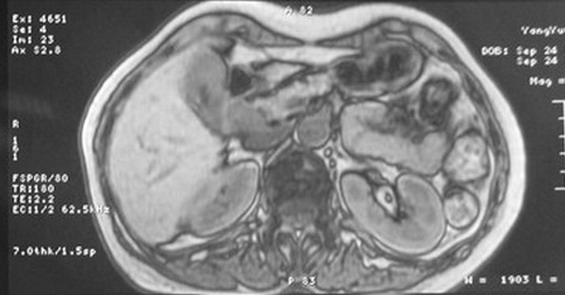

标题: MRI2066:腹膜后占位,请会诊,CT18531近期扫描图像

无明显不适,体检发现,

mri基本排除血管类肿瘤,明显强化说明极富血供,临床无症状,考虑胰岛细胞瘤可能大。

强化明显,并见有血管与之相连;考虑巨淋巴增生症.

极富血供的占位性病变,首先考虑良性,期待结果。